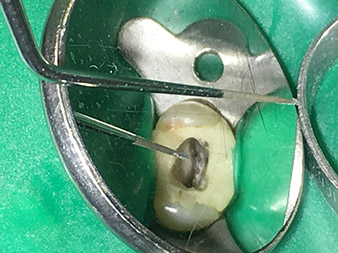

Neben effizienten Diagnose- und Behandlungsmethoden zählt der Einsatz neuester technischer Hilfsmittel und Instrumente zu den wichtigen Bausteinen einer erfolgreichen Patienten-Betreuung. Pro Woche kümmert sich Dr. Shahrad Nouraie Ashtiani zusammen mit seinem Team in der Praxis in Bremen (Deutschland) um bis zu zehn Endofälle. Die Forderung der Patienten nach einer möglichst schonenden Behandlung sowie guten Erfolgsprognosen bedeutet für den Zahnarzt und Weiterbildungsassistenten der Oralchirurgie mit Tätigkeitsschwerpunkt Endodontie eine tägliche Herausforderung.

Als Anwender des erweiterten W&H Instrumenten-Sortiments für die Ultraschall-Endodontie gelingt es Dr. Nouraie Ashtiani Wurzelkanalbehandlungen nicht nur effizienter, sondern vor allem mit weniger Belastung für den Patienten durchzuführen. Selbst schwierige Situationen werden vom Experten mühelos gemeistert. In einem Interview spricht der Endodontie-Spezialist über die besonderen Eigenschaften der W&H Instrumente und verweist auf mögliche Risiken in der Wurzelkanalbehandlung.

Fotos: Dr. Shahrad Nouraie Ashtiani, Bremen